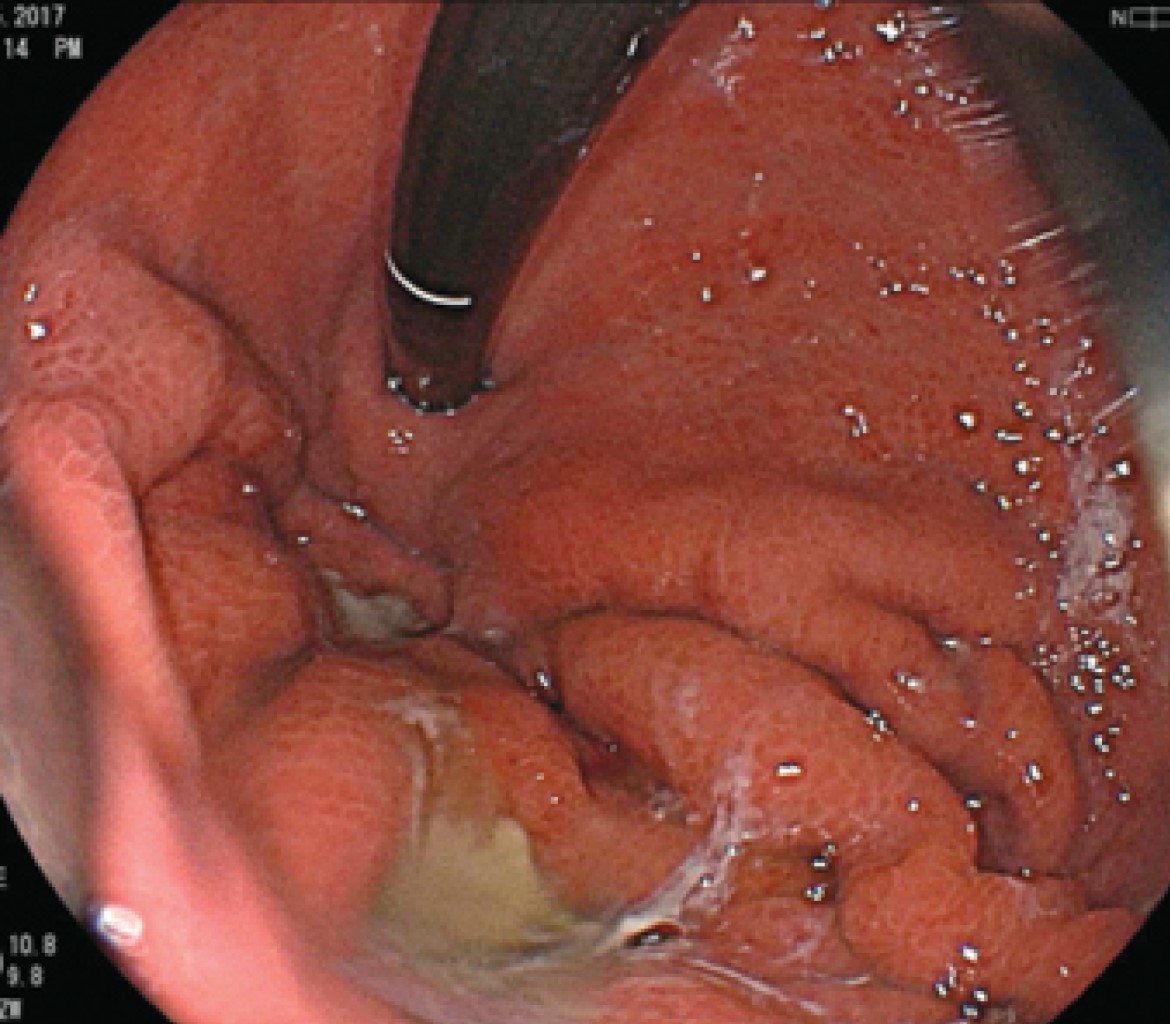

Introducción: La prevalencia de cáncer gástrico en México ha tenido un incremento en los últimos años con predominio en hombres. Los factores de riesgo son el consumo de alcohol, tabaco e infección por Helicobacter pylori, considerado en nuestra población como de riesgo moderado. Aunque el adenocarcinoma sigue predominando como la neoplasia maligna gástrica más frecuente, un porcentaje no despreciable del 7-8%, según la Organización Mundial de la Salud, lo ocupa el linfoma no Hodgkin (extranodal) y los leiomiosarcomas. El adecuado abordaje diagnóstico y la diferenciación son cruciales entre el adenocarcinoma y el linfoma, ya que de ello depende el pronóstico y el tratamiento. Caso clínico: Se comunica el caso de un hombre de 79 años con astenia, hipercalcemia maligna con hallazgo incidental de engrosamiento gástrico por tomografía. Se realizó ultrasonido endoscópico para el diagnóstico de linfoma gástrico de variedad difuso (Ann Arbor modificada II2). Revisión de literatura: El ultrasonido endoscópico es considerado una herramienta para el diagnóstico de neoplasias malignas gástricas en todas sus variantes, principalmente donde la enfermedad se encuentra en capas profundas. Conclusión: El ultrasonido endoscópico es el método que nos lleva a obtener alta precisión diagnóstica en linfoma gástrico permitiendo la toma de biopsias del espesor total de la pared de bloque celular para realizar diagnóstico diferencial siempre con inmunohistoquímica.

Figura 4